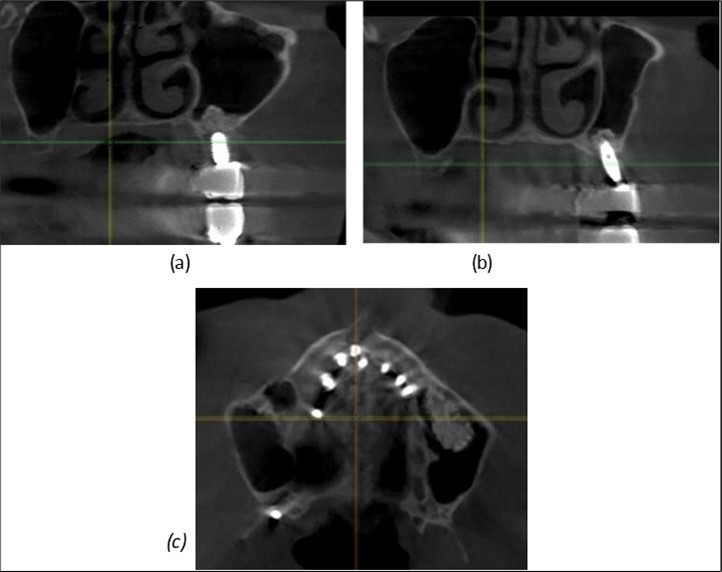

A total of 11 implants is placed in the maxilla, including compressive TPG implants with a polished surface in the maxillary-sphenoid fusion area (Figure 3, Figure 9). Similarly, in the anterior region, final fixation is achieved in the nasal cortex, and BCS corticobasal implants are added in areas with massive bone loss in the frontal region (Figure 3, Figure 8, Figure 11). Additionally, in the palatal sinus cortical area, with the aim of avoiding the addition and sinus lift zone where the second cortical bone no longer exists, 3 implants are placed, 2 in quadrant 1 and 1 in quadrant 2 (Figure 3, Figure 8). Through the Caldwell-Luc sinus lift procedure, the sinus cortical bone is displaced to allow the placement of the graft material and elevation of the sinus membrane. This sinus cortical is no longer recreated at the junction of the graft material and mucosa-sinus membrane, making it impossible to place a corticobasal implant, which relies on the second cortical bone. In the distal mandibular area, after the removal of two stage implants due to massive destruction in quadrant 3, implant placement distal to the mylohyoid line is not possible, as in quadrant 4 (Figure 10). A re-intervention occurs after 5 months to stabilize the area (Figure 12, Figure 14). Also, at the moment of fixation, the tip of one implant fractures, and the decision is made to leave it in place due to regional bone destruction, in order to avoid enlarging the bone defect.

Figure 8.(a), (b) Sinus lift and grafting area with two stage implants before their removal. (c) area of fixation of BCS and TPG implants, avoiding the sinus lift and grafting area

Figure 9.Implants in the pterygoid plateau area: (a) TPG implant fixed in the maxillary-sphenoid junction area, quadrant 1; (b) TPG implant fixed in the maxillary-sphenoid junction area, quadrant 2.

Figure 10.Implants in the palatal sinus cortical area to avoid bone grafting: (a) BCS implant partially fixed in the graft material mass, partially in the palatal cortex; (b) Implant fixed in the palatal cortex at the junction with the nasal cortex, behind the graft material mass.

Figure 11.Implants in the anterior area anchored in the nasal cortex (BCS and TPG): (a), (c) – BCS implants fixed in the nasal cortex; (b), (d) – TPG implants fixed in the second nasal cortex with compression in the trabecular area.